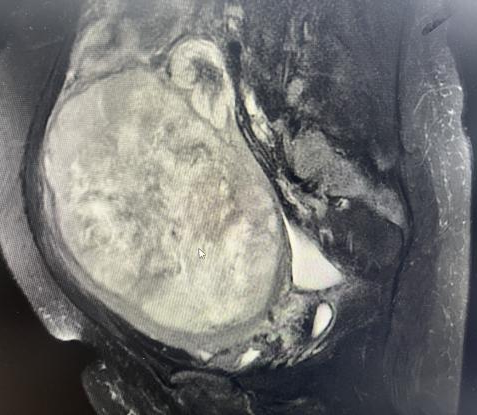

检查结果令人扼腕:王阿姨的盆腔内有一个巨大的肿瘤,考虑为子宫恶性肿瘤。充分评估后我们为她实施了“经腹全子宫+双侧附件切除术”,术后病理诊断揭开了真相——高级别子宫内膜间质肉瘤,一种恶性程度较高的子宫恶性肿瘤。由于发现较晚,肿瘤已经长得非常大,错过了最佳的早期治疗时机。

认识“子宫肉瘤”——隐匿的杀手

王阿姨所患的“高级别子宫内膜间质肉瘤”属于子宫肉瘤的一种。这是一种起源于子宫肌层或子宫内膜间质的恶性肿瘤,相对于常见的子宫内膜癌,它更为罕见,但恶性程度更高,进展更快,早期症状也不典型。

温馨提示:手术实况图像可能引起不适,非专业人士请勿点击浏览。